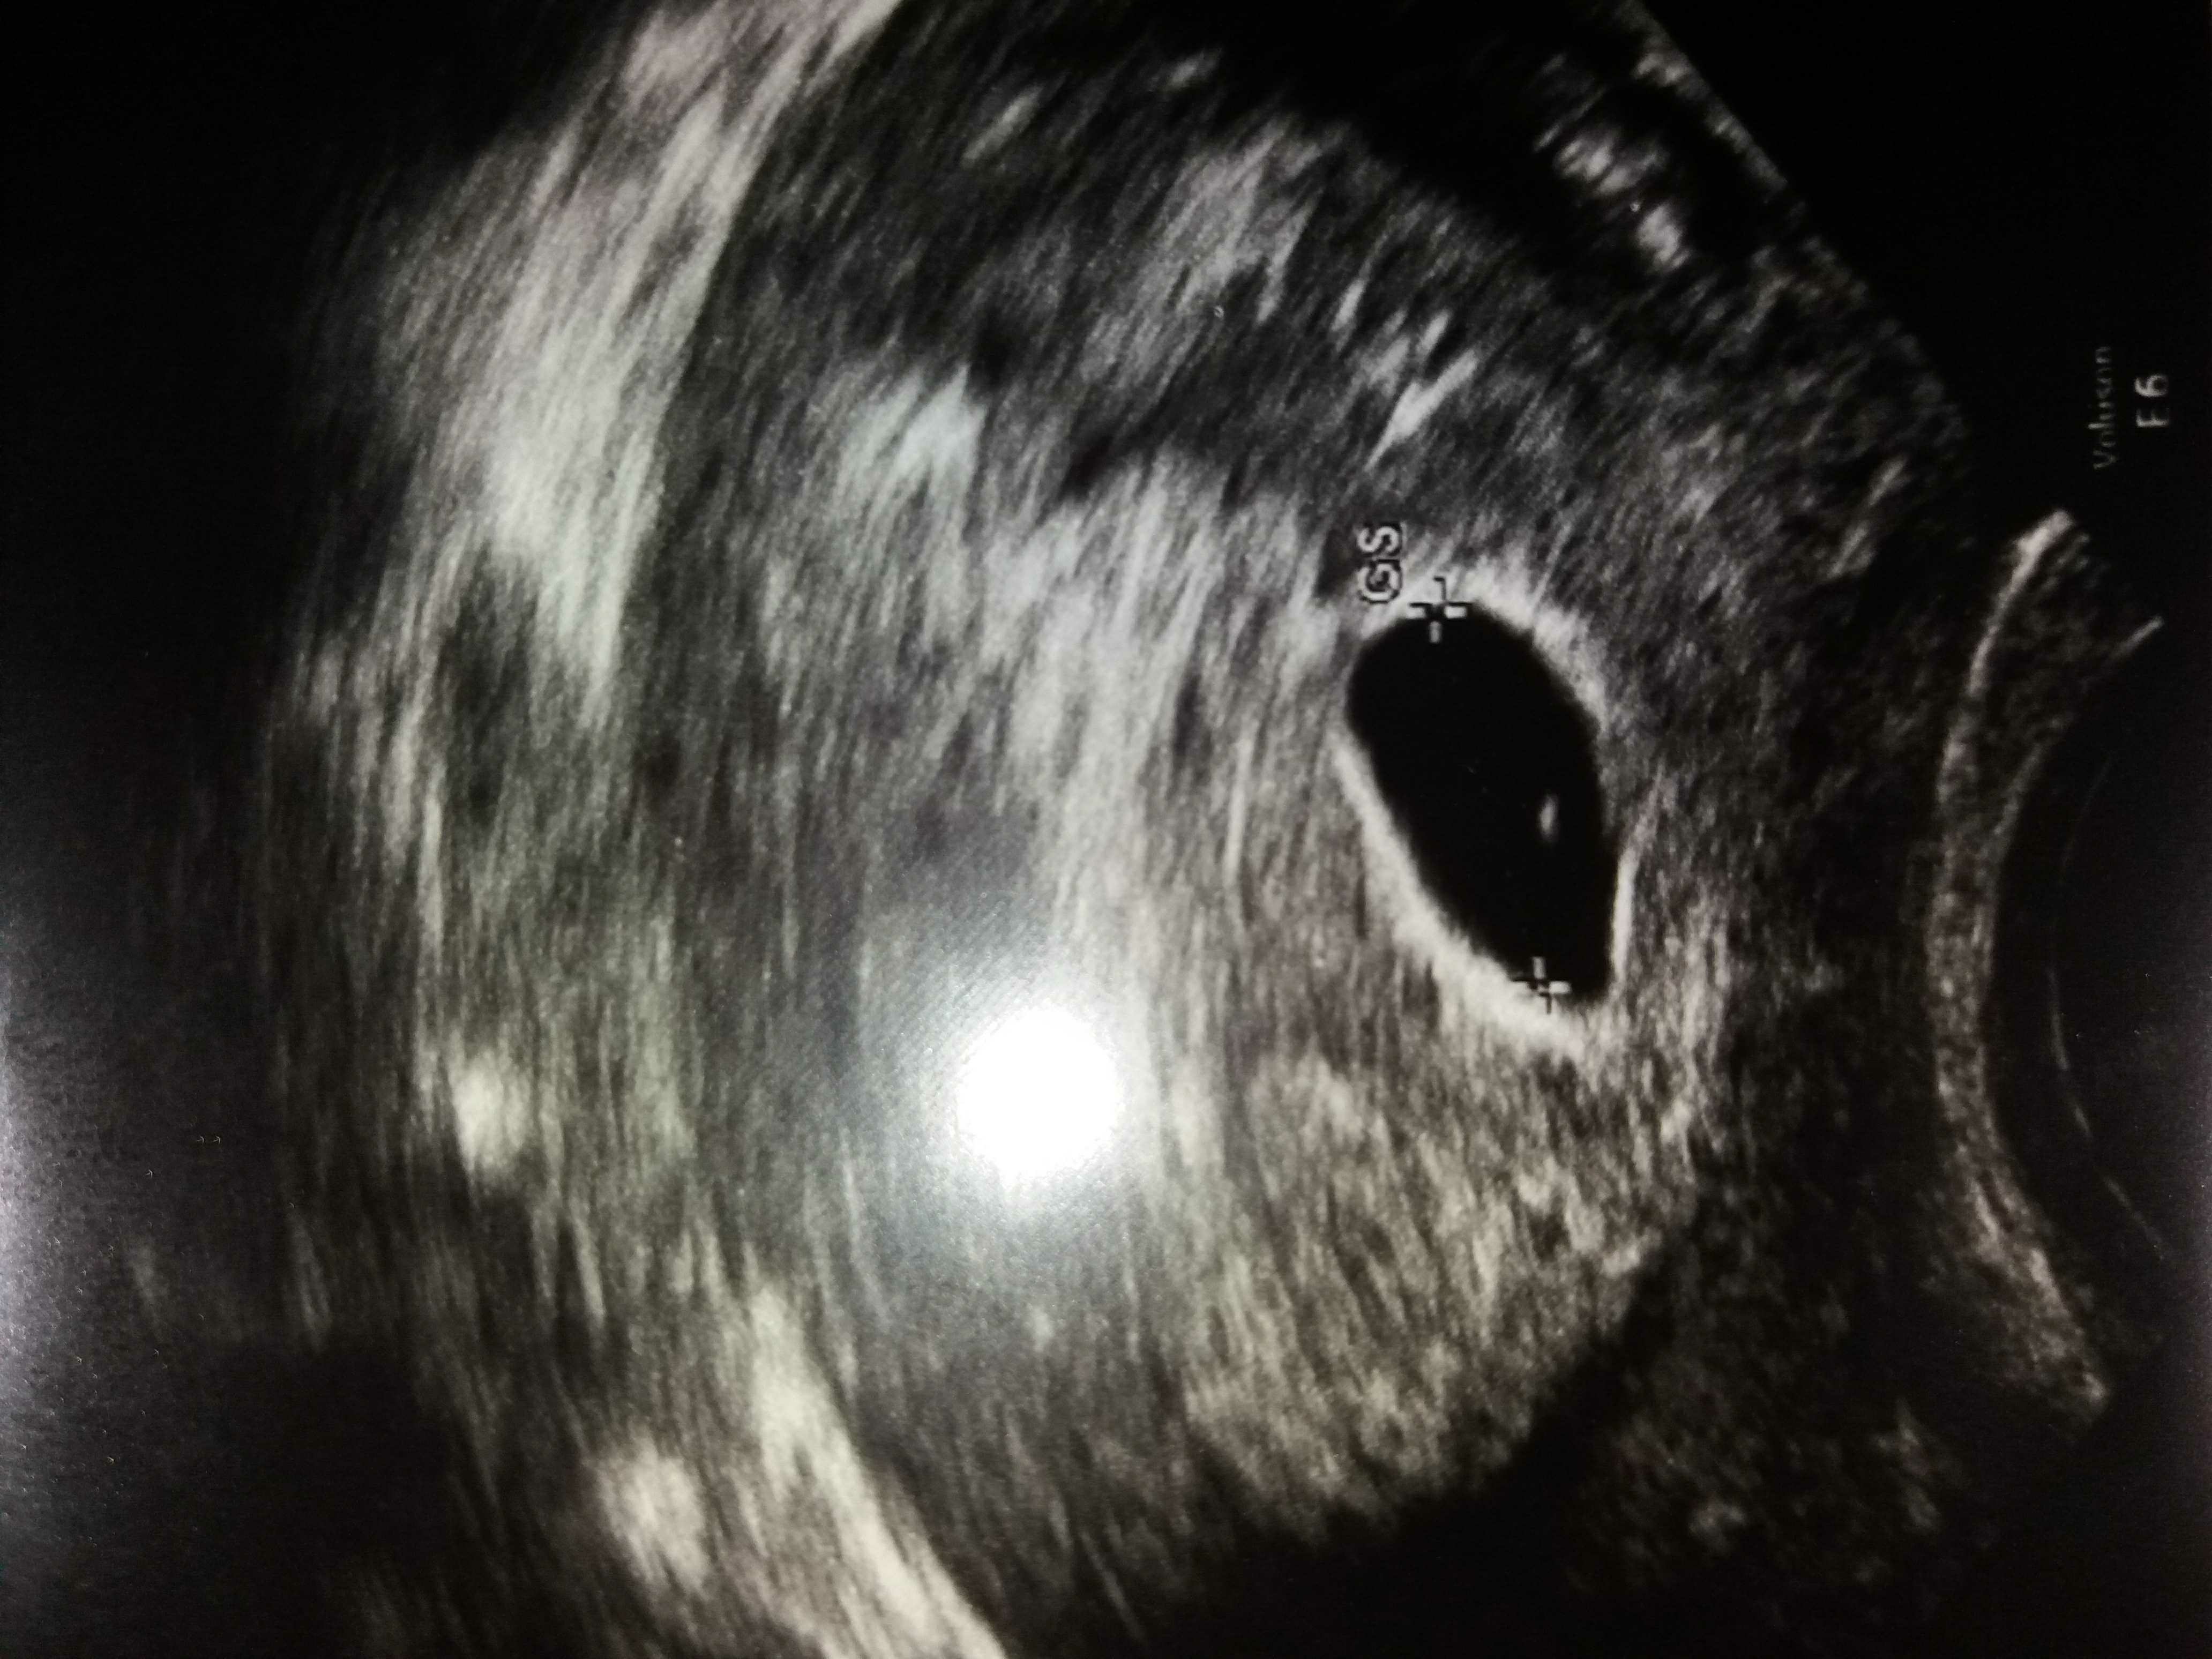

Dziewczynki tak sie przygladam temu mojemu pierwszemu zdjeciu USG i porownuje z innymi na Google i wydaje mi sie ze przy tej wielkosci pecherzyku ciazowym (12mm) to powiniem byc bardziej widoczny pecherzyk żółtkowy :( A u mnie tylko taka mala kropeczka jest... Pamietacie jak u Was bylo na pierwszym USG zanim pojawil sie zarodek? Cos sie boje ze on jest duzo duzo za maly... :( Zobacz załącznik 874336

to chyba takie ujęcie, wyostrzone na największy wymiar pęcherzyka ciążowego, ja mam kilka zdjęć i na każdym pęcherzyk żółtkowy inny - jak mierzył zarodek to pęcherzyk był nieostry i mniejszy niż na tym na którym mierzył pęcherzyk więc wszystko jest ok!

No tak logicznie mowisz... rzeczywiscie czesto ten pecherzyk ma taka jasna otoczke na zdjeciach ktora ledwo widac. Ale dziwne ze mojego nawet nie mierzyl... No bo co innego to moze byc? Zarodek na pewno nie.